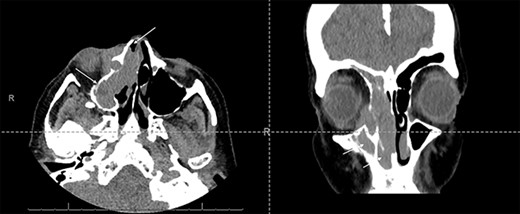

Fine-needle aspiration of a right neck lymph node showed reactive hyperplasia, with no evidence of dysplasia or malignancy. Computerized tomography (CT) imaging showed an extensive soft tissue mass within the right maxillary sinus, extending into the right nasal cavity and orbit (Fig. 1).

Axial and coronal CT sinus images showing an extensive soft tissue mass within the right maxillary sinus which completely obliterates the sinus cavity and extends into the right nasal cavity (arrows). It also involves the right ethmoid and frontal sinuses. The mass extended through the lamina papyracea into the right orbit, abutting and displacing the globe, and is seen to invade the nasolacrimal system.